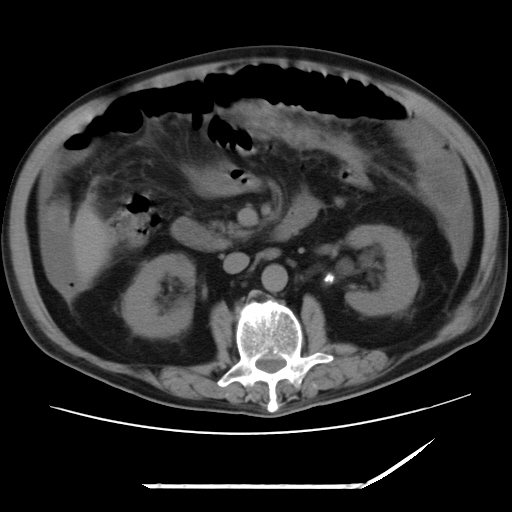

以下是引用zxl51642在2009-8-12 18:55:00的发言:[br]1、肠系膜脂肪浑浊,密度增高,腹水,支持腹膜炎诊断;2、右肾盂及输尿管中段结石,左输尿管起始段结石;3、胆囊切除术后改变?4、双侧胸膜腔少量积液;5、胰腺体积不大,勾勒清楚,肾前筋膜无增厚,不支持胰腺炎,请结合血尿淀粉酶及临床。